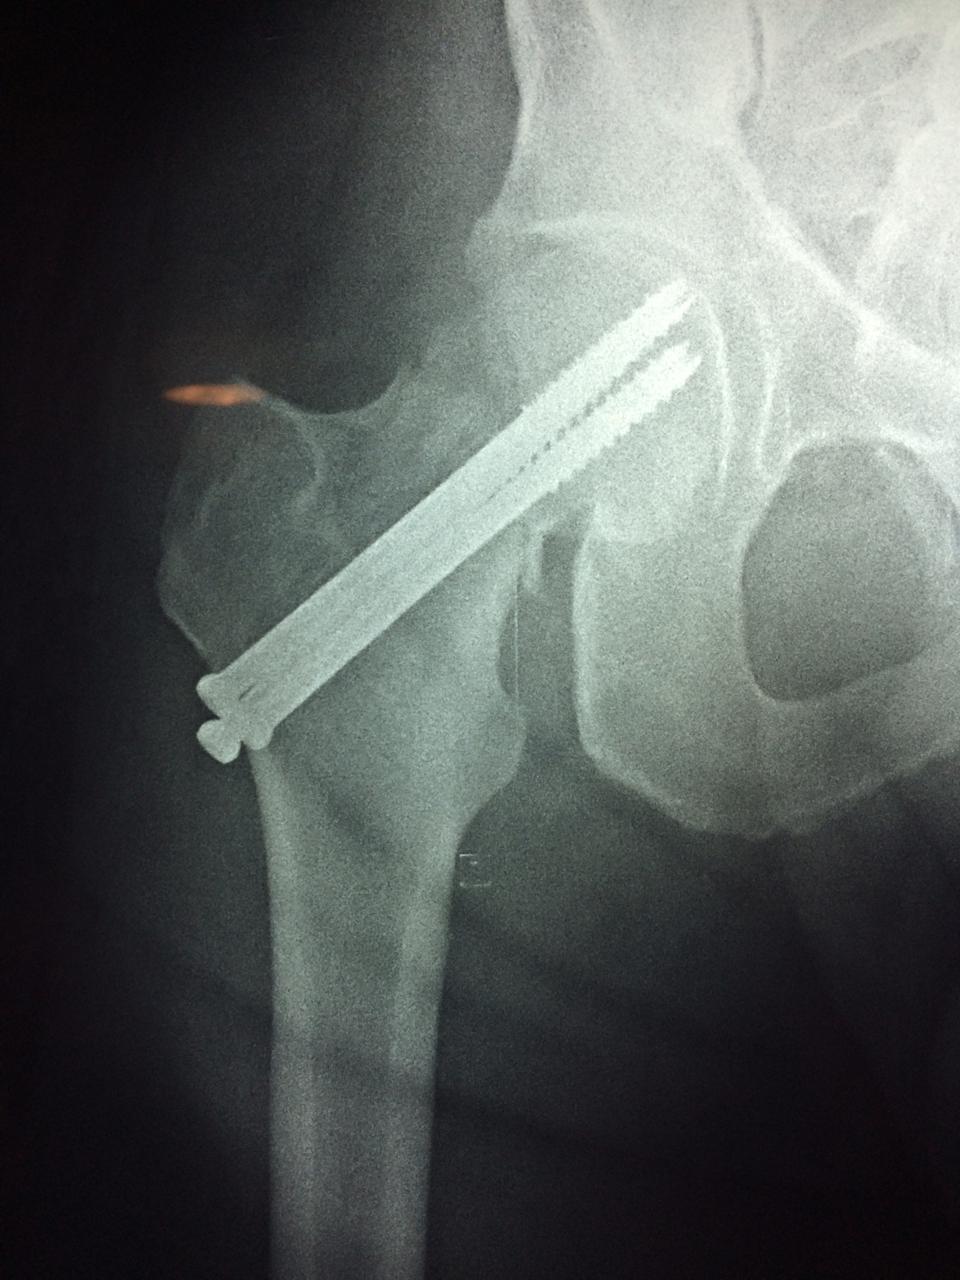

La cirugía de fractura de cadera se realiza para reparar una ruptura en la parte superior del hueso del muslo. Este hueso se denomina fémur.

Es parte de la articulación coxofemoral. Si una fractura de cadera no recibe tratamiento, es posible que deba permanecer en una silla o en la cama.

Esto puede llevar a otros problemas de salud potencialmente mortales, sobre todo si usted es una persona mayor.

A menudo se recomienda la cirugía para reparar la fractura debido a dichos riesgos.